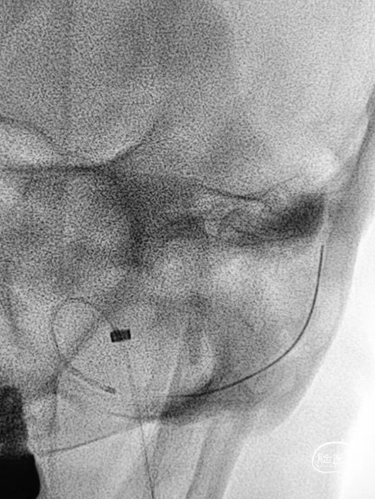

➤DSA

6F 长鞘导引至左侧颈内静脉末端。

测压导丝对横窦至乙状窦进行测压,静脉压差<2mmHg,未对狭窄段进行球囊扩张。

6F 长鞘导引至左侧乙状窦。

交换Command 18导丝超选至左侧横窦,将Echelon-10微导管置入静脉窦憩室。

路图下,沿Command 18导丝将8×40mm Xpert Pro支架输送至乙状窦,使用支架近远端marker点进行准确定位,整个推送过程顺利,无明显阻力。

Xpert Pro支架未展开状态下在憩室内尝试使用弹簧圈进行填塞,发现成篮困难。

随即释放Xpert Pro支架以覆盖憩室开口,支架打开后显影清晰,贴壁良好。使用微导管穿出支架网孔,并置入憩室内进行弹簧圈填塞。单微导管填塞过程弹簧圈成篮较为困难。

使用双导管继续在Xpert Pro支架辅助下进行弹簧圈填塞,再次造影显示:憩室内血液已完全阻滞,未见显影。

Xpert Pro支架在乙状窦内形态良好。静脉窦憩室闭塞完全。